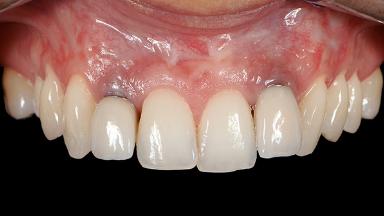

A 30-year-old woman was referred by her general dentist for evaluation of an esthetic complication related to previous implant treatment for congenitally missing maxillary lateral incisors. The patient’s chief complaint was the inadequate esthetic appearance of her smile. The case demonstrates the use of a combined approach to achieve optimal results. Two different flap designs - a tunnel technique and a coronally advanced flap - are employed based on the surgical objectives for the affected site.

Soft Tissue Grafting Yes